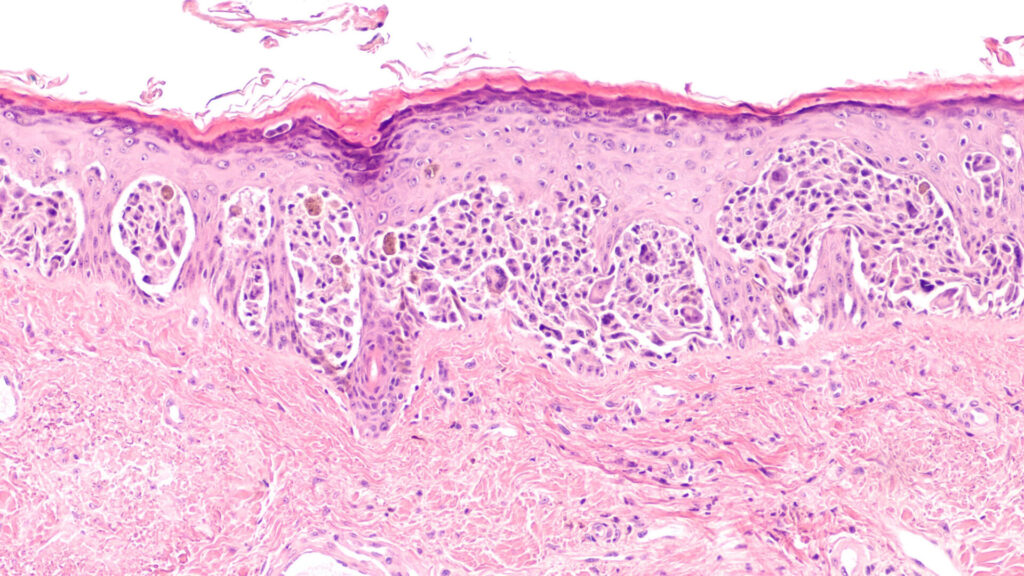

A biopsy is a procedure where a sample of the skin or tissue is removed and sent for microscopic examination. There are several types of biopsies such as punch, shave, excisional and incisional biopsies.

A biopsy is performed to determine if a suspicious mole or spot on the body is cancerous, or to assist in diagnosing a lesion or skin condition.